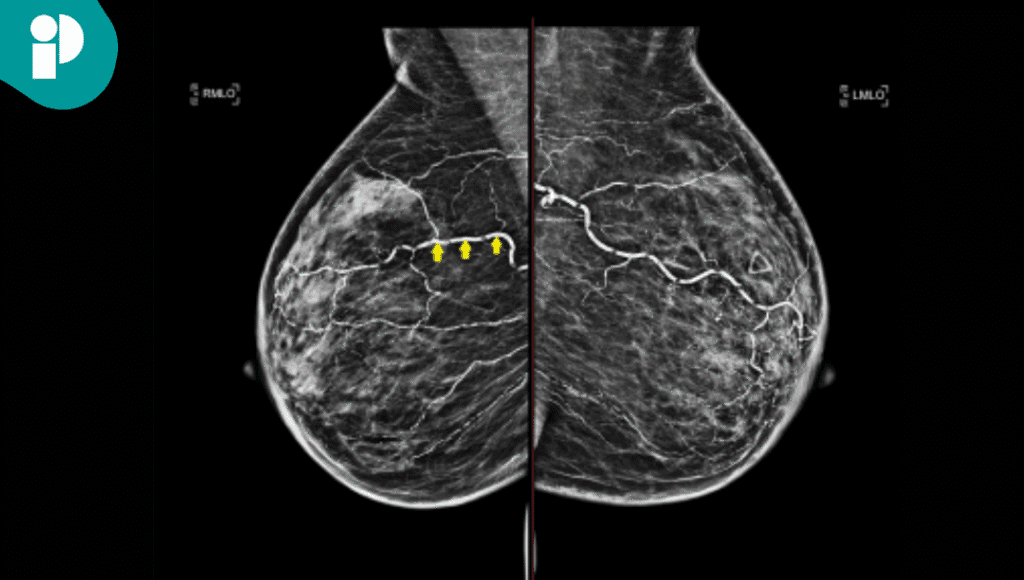

Las pruebas iniciales generaron confusión diagnóstica. La mamografía mostró extensas calcificaciones en la pared arterial sin una masa definida. En contraste, la ecografía reveló una masa heterogénea y mal definida. Debido a que la lesión aumentó de tamaño en un período de cinco meses, se optó por la escisión quirúrgica.

El análisis histopatológico de la muestra fue clave. Reveló una extensa necrosis grasa y una calcificación vascular generalizada en un patrón similar a la esclerosis de Mönckeberg. La severidad de la calcificación fue tal que causó una oclusión vascular completa focal, resultando en un infarto de la grasa mamaria.